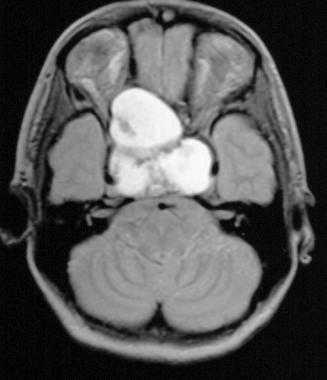

Коллоидная киста - это врождённое нейроэпителиальное образование. Коллоидная киста выстлана эпителием и имеет фиброзную капсулу. Она составляют около 1-2% объемных внутричерепных образований. Обычно диагностируются в возрасте между 30 и 50 годами. При МРТ головного мозга видно, что киста всегда расположена в переднее-верхнем отрезке III желудочка между отверстиями Монро. Контур ее четкий, форма округлая, содержимое бывает неоднородное. Размер от 3 мм до 4 см, при больших размерах она закрывает отверстия Монро и вызывает окклюзионную гидроцефалию. Сигнал зависти от примеси белка к ликвору. При наличии белкового мукоидного содержимого киста гиперинтенсивна на Т1-взвешенных МРТ и гипоинтенсивна на Т2-взвешенных МРТ, но встречаются варианты гиперинтенсивные на томограммах обоих типов кольцевидные или смешанные . Контрастирования не наблюдается.

КТ и МРТ головного мозга. Коллоидная киста III желудочка.

Коллоидная киста - это врождённое нейроэпителиальное образование. Коллоидная киста выстлана эпителием и имеет фиброзную капсулу. Она составляют около 1-2% объемных внутричерепных образований. Обычно диагностируются в возрасте между 30 и 50 годами. Всегда расположена в переднее-верхнем отрезке III желудочка между отверстиями Монро. Контур ее четкий, форма округлая, содержимое бывает неоднородное. Размер от 3 мм до 4 см, при больших размерах она закрывает отверстия Монро и вызывает окклюзионную гидроцефалию. Сигнал зависти от примеси белка к ликвору. При наличии белкового мукоидного содержимого киста гиперинтенсивна на Т1-взвешенных МРТ головного мозга и гипоинтенсивна на Т2-взвешенных МРТ, но встречаются варианты гиперинтенсивные на МРТ головного мозга обоих типов взвешенности кольцевидные или смешанные. При МРТ головного мозга с контрастированием усиления сигнала не наблюдается.